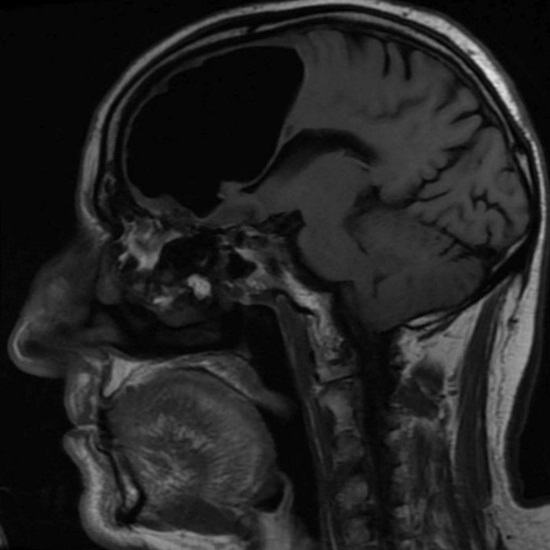

Észak-Írország orvosai meglepődtek, amikor megvizsgálták őket nemrégiben egy 84 éves beteg, aki rossz közérzettel jött hozzájuk. Miután elvégezték az ember fejének mágneses rezonancia leképezését, az orvosok váratlanul rájött, hogy hiányzik a jobb frontális része az agy lebenye. Ehelyett a nyugdíjas koponya levegő volt zsebében. Aztán az orvosok megállapították, hogy a tényleges agyrészlet a beteg sehol sem tűnt el, hanem keverte ezt a kóros irányt az üreg.